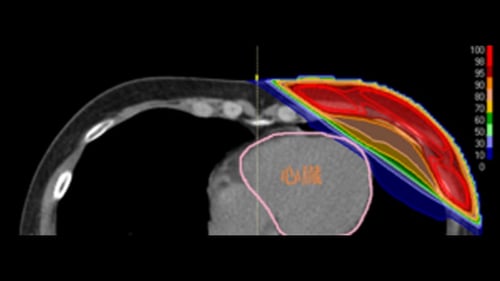

・乳がん

主に手術のあとの術後照射の適応となります。患側の全乳房に対して再発リスクを低減するために放射線治療を行います。腋窩リンパ節転移の有無により同側頚部へも照射することがあります。乳房温存術後の方は17回の短期照射を行っています。乳房切除・腋窩リンパ節郭清後の方は25回の治療となります。切除断端が陽性の場合は5回程度の追加照射を行います。副作用は皮膚炎(発赤、着色、日焼け様症状)、倦怠感、創部皮膚硬結、放射線肺炎(稀:咳、発熱、呼吸苦など)、リンパ浮腫などが起こりえます。(図:乳がんに対する放射線治療)

左乳がんの術後照射には、深吸気息止め照射(DIBH)を行っており、心臓への放射線の影響を低減することが可能です。(上図:DIBHなし 下図:DIBHあり)